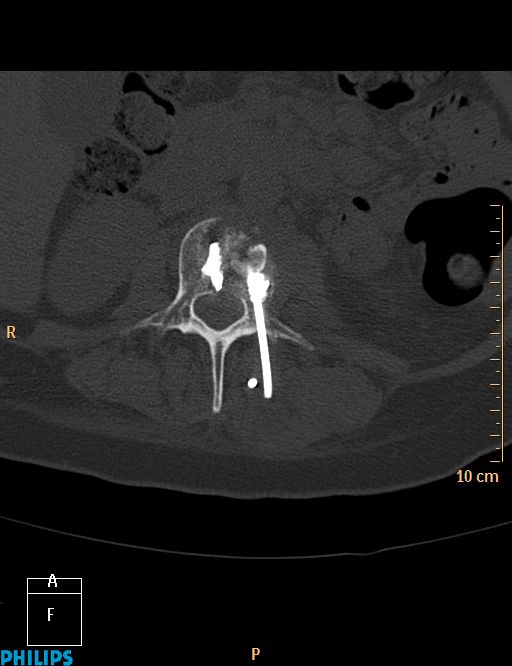

La vertébroplastie C'est ça d'attendre trop avant de retirer le trocard !!!